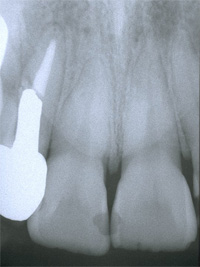

| 失った部分にインプラントを1本埋入します。従来は健全な両隣の歯を削ってブリッジを用いて治療していましたが、インプラントを用いると健全な歯を削ることなく治療を行うことが出来ます。 |